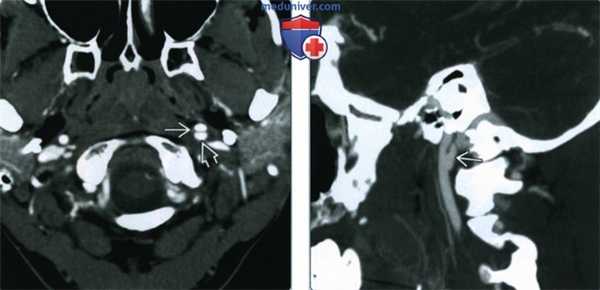

(Слева) КТ-ангиография, аксиальная проекция, пациент 29 лет с переломами шейного отдела позвоночника в результате мотоциклетной травмы. Имеются отклонения со стороны верхнего сегмента левой внутренней сонной артерии: признаки расслоения с формированием лоскута интимы и образованием кармана вдоль задней стенки сосуда.

(Справа) КТ-ангиография, реконструкция в сагиттальной проекции, этот же пациент. Четко визуализируется псевдоаневризма, которая возникла на фоне расслоения внутренней сонной артерии. Обратите внимание, что сагиттальные срезы, в отличие от аксиальных, позволяют получить четкую картину этого состояния. (Слева) КТ-ангиография, коронарная проекция. Женщина 44 лет с фиброзно-мышечной дисплазией: определяется нечеткость контуров обеих внутренних сонных артерий, которая весьма характерна для фиброзно-мышечной дисплазии. В левой сонной артерии имеется участок расслоения с формированием псевдоаневризмы.

(Справа) КТ-ангиография, реконструкция в сагиттальной проекции, этот же пациент. Четко визуализируется псевдоаневризма, которая возникла на фоне расслоения внутренней сонной артерии. Обратите внимание, что сагиттальные срезы, в отличие от аксиальных, позволяют получить четкую картину этого состояния.